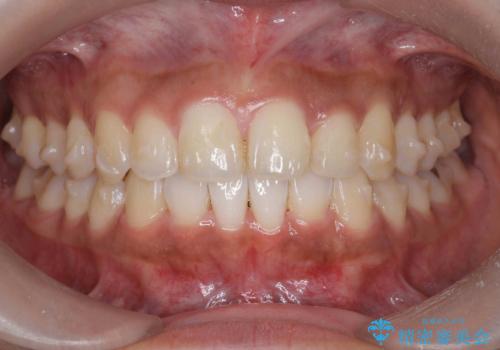

- 前歯のガタつき、突出感のある前歯の改善を求めて来院されました。

前歯の角度を改善し審美性を高めるとともに、奥歯のガタつきも並べ直すことで安定した咬合関係の確立を目指します。

歯列の側方拡大をしっかりと行ったことで歯を抜かずに前歯の角度をしっかりと改善することができました。